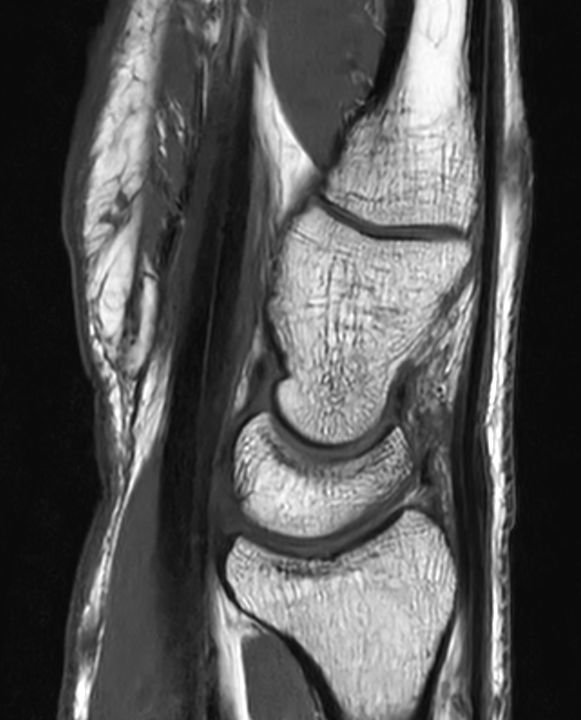

Wrist imaging case, leveraging Philips SmartSpeed, our breakthrough new MRI application that delivers image and speed without compromise. Building on our proven technology and leveraging AI* to take fast MRI technology to the next level. Imaging speed is increased while providing greater resolution to deliver outstanding image quality.

Sagittal T1w TSE

Sagittal T1w TSESmartSpeed

Sagittal T1w TSESmartSpeed Resolution